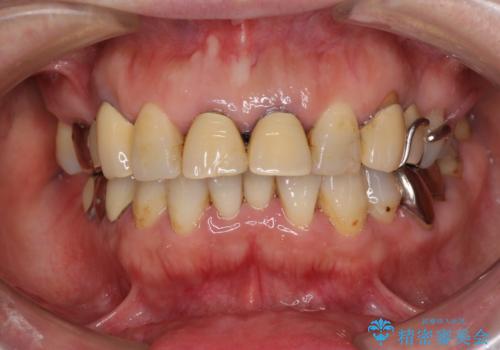

- 歯茎からの出血、入れ歯、歯の欠損、デコボコの前歯などを気にして来院された患者様です。

大の歯科治療嫌いとのことでしたが、今回の治療を契機にしっかりと治療を行いたいとのことでした。